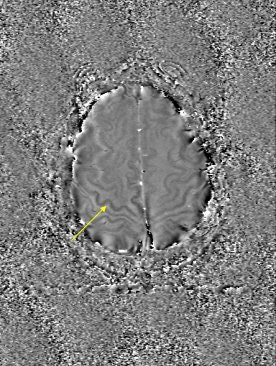

In traditional diffusion-weighted imaging (DWI) for stroke, "you'd look at this for cellular disruption, and you'd see quite clearly the major region affected by the stroke," he said. "DWI is often very broad. In the SWI image, you are seeing evidence of dramatic changes in oxygen saturation and maybe other sources of susceptibility. We can see the source of the stroke and maybe the vascular territory affected (see below). The hypothesis is that the deoxyhemoglobin content of the small vessels has increased over their normal values due to slower or restricted flow, making these (vessels) visible when they would normally not be visible."

| Stroke imaging with SWI. Although the DWI image (above) shows the affected region well, the details of the stroke are shown in the SWI image (below). Images courtesy of Dr. Daniel Wycliffe, Loma Linda University, Loma Linda, CA. |